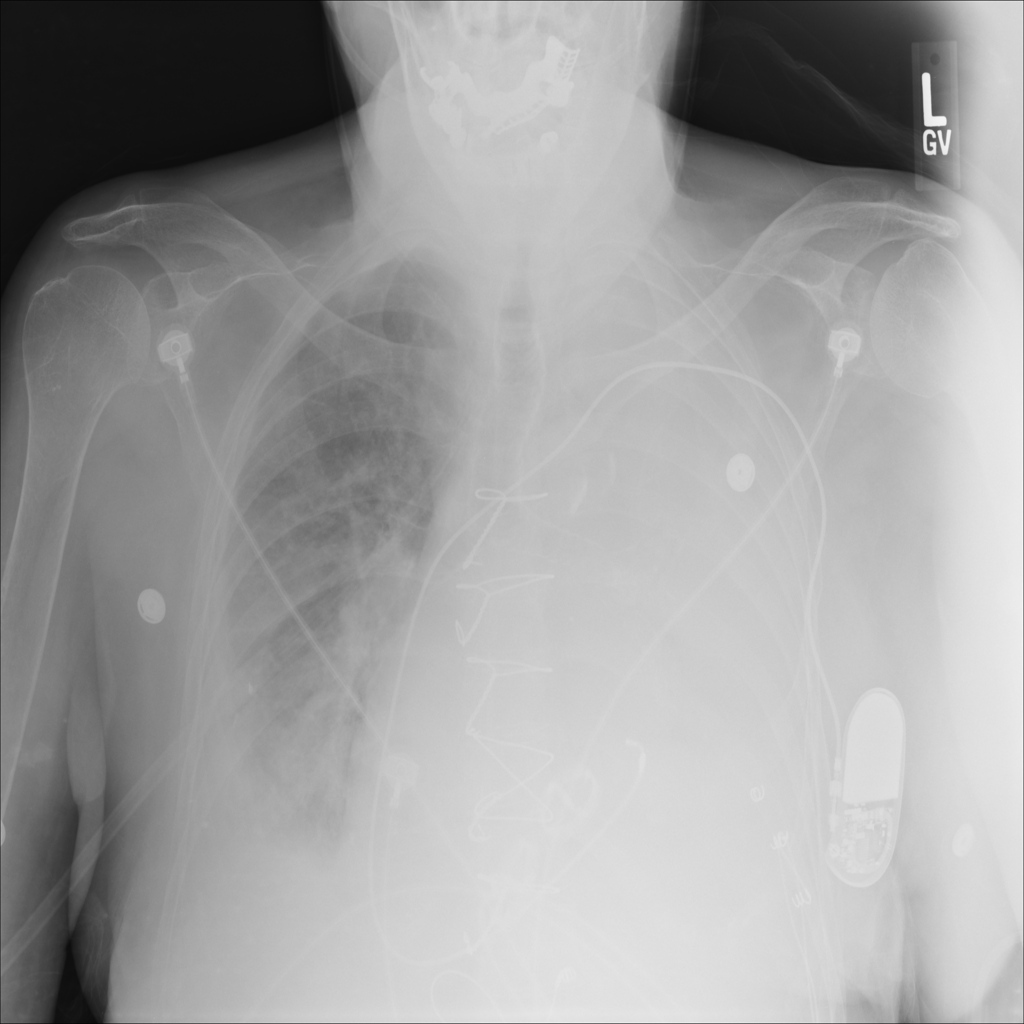

PAT-86C8 · IMG-000Effusion

PAT-86C8 · IMG-000

PA